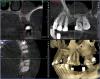

x3m Опубликовано 6 сентября, 2013 Автор Поделиться Опубликовано 6 сентября, 2013 (изменено) тест на витальность сейчас не проводился. мотивировать пациента не хочу - я рассказал свое видение ситуации.послушав авторитетные мнения, рассказал о вариантах на тему и прогнозах.дал ссылку на форум.написал письмо с вопросами автору установки имплантатов.созванивался и общался с этим же автором.как мне показалось, этого вполне достаточно, чтобы пациент самостоятельно принимал решение. теперь о вопросах.1. Где находится имплантат 16? Почему не видно кости?Визуально виден доступ в этой зоне: разрез от 14 до бугра по вершине а/о ...и торчащие заглушки. т.к. от доктора инфы я не получил, подозреваю открытый синус? меня смущает отсутствие кости у 16, реакция слизистой в гайморовой, положение платформы относительно 15 (с оглядкой на будущее протезирование), габариты будущей коронки на 16 (КТ в окклюзии). 2. наличие кортикалки вестибулярно у имплантата в позиции 15 - где она? 3. Четвертый сегмент. 45 и 46-й платформами находились над силизистой.В этот визит проводилось протезирование 4 сегмента.насколько я понял, протезирование (+44 консоль) - временное (пластмассовая облицовка), хотя... для чего оно здесь? вероятно, оно-таки постоянное (пациент не знает, доктор информацию не раскрыл)). Коронки - массивные нависающие края (2-3мм вглубь при зондировании микрорезьбы), формат коронок с отрицательным углом, под балконом - отложения налета, легко кровоточащая десна... еще смущает глубина погружения имплантатов вестибулярно - кмк, в кости лишь половина макрорезьбы... какой прогноз? фото пока выложить не могу, постараюсь на след.неделе. 4. второй сегмент.Что делаем с 27,28? Думается, удаление 27,28 и откр. синус.реакция в гайморовой - затёк из кармана? 5. 36. несколько смущает ось и погружение.хотя изо всего установленного это самый неплохой)) 6. Состояние во фронтальном участке после костной пластики.материал не там, где хотелось бы.остатки под носовым ходом (красным), объема ни вестибулярно, ни по высоте нет.автор предложил имплантацию в этой зоне не рассматривать.Линия улыбки, в принципе, невысокая, но не хочется, чтобы перегружали 11 и 23 мостом с розовой керамикой... Какова вероятность восстановления объема аутоблоками?(желтым указана небная кортикалка). Коллеги, буду благодарен за попунктовые ответы п.с. сорри за много букоФ и картинкоФ Изменено 6 сентября, 2013 пользователем x3m Ссылка на комментарий

Bier Опубликовано 12 сентября, 2013 Поделиться Опубликовано 12 сентября, 2013 1. имплантат 16з стоит своей частью в полости пазухи, выполнен синуслифтинг. Вокруг имплантата виден остеотропный материал слабо рентген контрастный. Своей коронарной частью имплантат стоит в мягких тканях на 4 мм, что делает прогноз на его дальнейшую жизнь сомнительным. 2. имплантат 15 з расположен слишком вестибулярно, кортикальная пластинка либо очень тонкая либо ее нет. Прогноз неблагоприятный.3. Необходимо как минимум перепротезирование. Прогноз оценивать исходя из наличия или отсутствия гноетечения и стабильности имплантатов. Возможно можно ограничиться увеличением ЗКПД и адекватным протезированием. При наличии гнойного перимплантита рекомендовано удаление. Прогноз сомнительный.4.Согласен, удаляем. Реакция в гайморовой может быть и от кармана, а может быть остаточными являениями. Не критичны для синуслифтинга.5.36I я бы сохранил.6.объем кости для имплантации неадекватный. Для восстановления аутоблоки прогноз сомнительный. Я выступаю либо за грамотновыполненный GBR либо за 3D по Кюри. 2 Ссылка на комментарий

x3m Опубликовано 18 сентября, 2013 Автор Поделиться Опубликовано 18 сентября, 2013 (изменено) протоколирование перед удалением:Алле- -АП! "Удалить за 0,60 сек.": - только что из лунки. на поверхности гной, ошметки кости и чуть свежей крови - видимо, не прижился ... кюретаж, губка в лунку, диплен сверху: ...и рентгенконтроль:смутило наложение тени на пульповую камеру (хочется, чтобы это была костная тень, а не дефект корня с перфорацией). Через 3 дня:подтверждение перфорации (инструменты не цепляют по дистальной стенке, ашка не уперлась ни во что и проскочила почти до апекса): При конденсации кальций тоже не вышел за канал (уф, полегчало): пока 3.3 решили не удалять, наблюдаем. Вопрос по клыку:какой прогноз и какие действия? да, меня вот еще что "несколько смущает" в 4 сегменте:состояние имплантатов в позиции 4.5, 4.6 после установки (апрель с.г.):вид сейчас: МК, шатающийся Clip F в шахте, обратный угол коронок с поднутрением (на фото - зондируем резьбу), там налет и легко кровоточит, язычно над десной - полированная шейка имплантата.а на КТ имплантат 45 в кости на 4мм вестибулярно...как это может работать в долгосрочном прогнозе??? Изменено 18 сентября, 2013 пользователем x3m Ссылка на комментарий